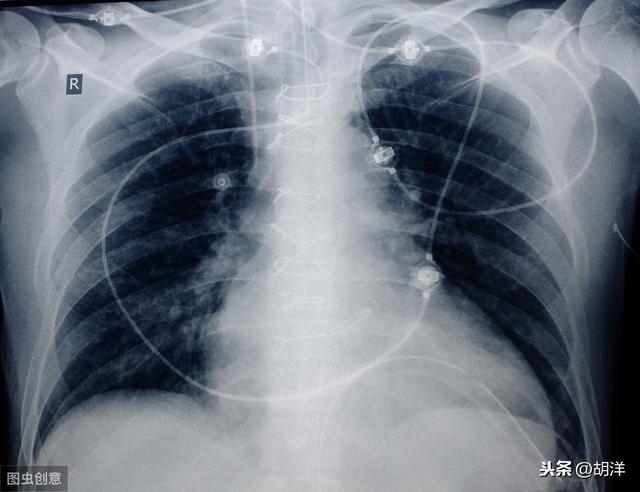

Ce patient n'avait que 39 ans, souffrait d'oppression thoracique et d'essoufflement, et on lui a diagnostiqué un adénocarcinome du côté droit du poumon, avec un épanchement pleural important et une perte de fonction de l'ensemble du poumon droit. Une affection aussi grave est plus fréquente chez les personnes âgées et, si elle n'est pas traitée, une insuffisance respiratoire se produira rapidement. Heureusement, elle est sensible à la thérapie ciblée et vit avec la tumeur depuis plus de trois ans maintenant, avec un épanchement pleural sous contrôle.